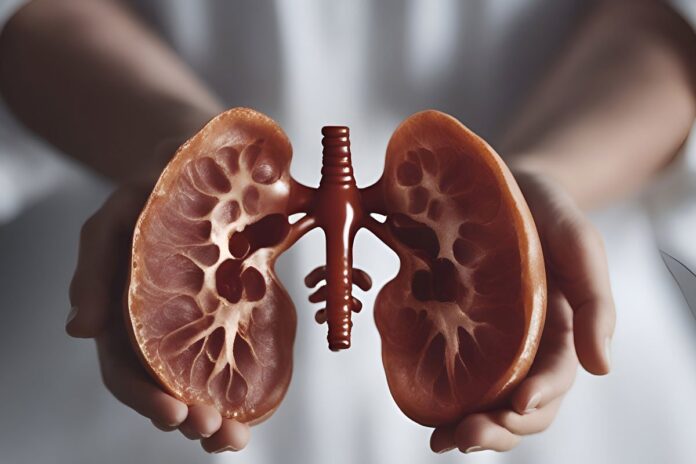

Bubrezi su tihi radnici našeg organizma – filtriraju krv, uklanjaju toksine i održavaju ravnotežu tečnosti.